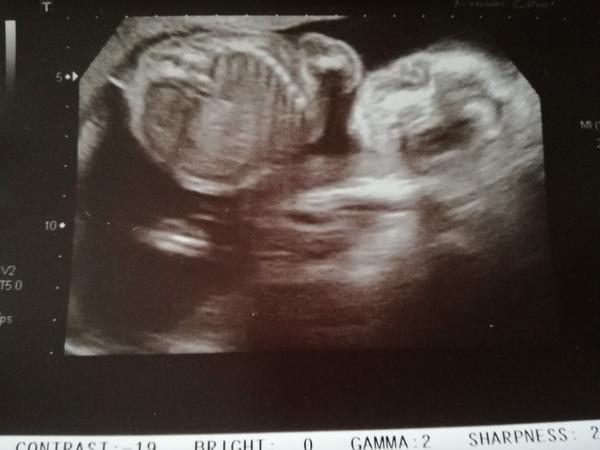

Je to holčička nebo chlapeček? Foto ultrazvuku

@kacasa ja si rikam, jestli to tam nemuze byt pupecnik nebo tak neco 😀 Ale dr. si byla docela jista..tak uvidime.

@verinikki Me treba rekli kluk a tak jsem se ptala na zkusenosti pač jsem si myslela,ze je to holka a nakonec to holčička je 💃 ono je to jedno nakonec to si jen kratime cas 😉